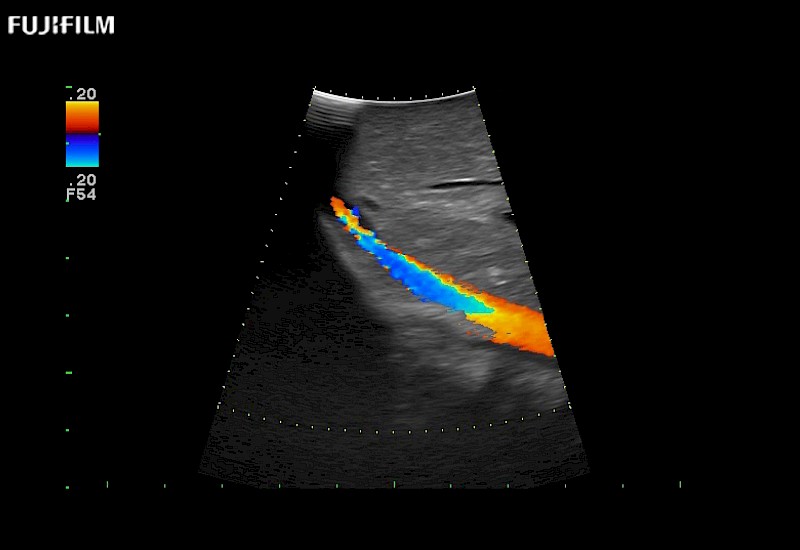

Our dedication to Surgical Oncology allows us to offer superior image quality, outstanding system reliability and intuitive use of cutting edge technology.